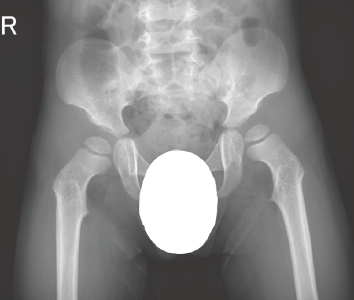

A. 両股関節正面像(8歳、男):腸骨稜のレース様所見と大腿骨頚部の短縮を認める。